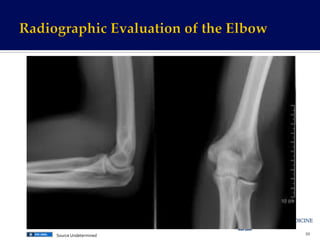

Undetermined

Anterior

Fat

Pad

“Sail

Sign”

Posterior

(Never

normal)

Humeral

Line

•

Normal

=

Middle

of

capitellum

Abnormal

1/3

or

completely

Radial-­‐Capitellar

• Normal

Transects

40